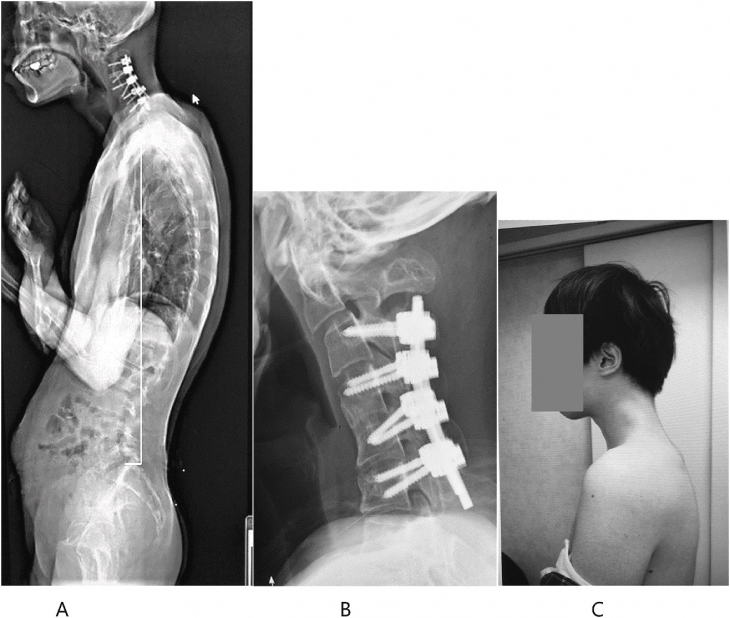

환자의 척추가 장기간의 부자연스러운 자세로 인해 크게 변형된 모습. 일본정형외과 학회지(JOS)의 사례 연구집 논문 캡처

정밀검사를 진행한 결과 목뼈가 왜곡되고 탈구됐으며, 시간이 지나면서 척추(특히 경막) 부위에 흉터 같은 조직이 증식한 것이 관찰됐다.

이에 의료진은 수술을 택했다. 먼저 척추뼈의 튀어나온 부분과 경막에 생긴 흉터 같은 조직 일부를 제거했다.

이후 목뼈에 나사와 금속 막대를 삽입해 자세를 교정했다.